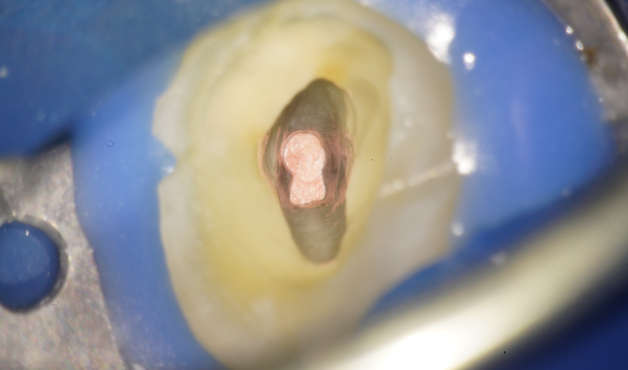

自家歯牙移植と根管治療で

天然歯を保存した症例

タップで写真の拡大ができます。

Before

Under Treatment

After

主訴

歯を残せないと言われた。インプラントは先延ばしにしたい

治療内容

自家歯牙移植 / イニシャルトリートメント(大臼歯)レジンコア

治療期間

2ヶ月

治療費用

308,000

治療の

リスク

術後しばらくしてから骨性癒着、外部吸収を起こす可能性があります。